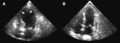

(A) Echocardiogram showing dilatation of the left ventricle in the acute phase. (B) Resolution of left ventricular function on repeat echocardiogram 6 days later.- ECG showing sinus tachycardia and non-specific ST and T wave changes from a patient with confirmed takotsubo cardiomyopathy.